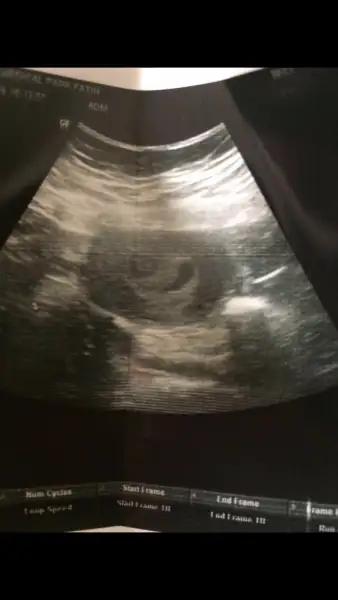

Bu bebeğin kesesi doktor verdi fotoğrafınıAma gebeliğimizi henüz çok yeni kese için 1500 bekemelisiniz

Maşallah değeriniz 19 ken ilk defa duydum gördüm. Bu arada beta hcg değeriniz 19 değil mi? Keseyi gördüğünüze göre tedirgin olmayın. Kaç mm keseniz?Bu bebeğin kesesi doktor verdi fotoğrafını

Sağlıklı bir gebelikte kanda beta HCG değeri 48 saatte iki kat artış gösterir.Gebelik kesesi vajinal ultrasonografi görülmeye başlanabilmesi için kandaki Bhcg düzeyinizin 1000-1500 ıu/ml seviyelerinde olması gerekmektedir. Karından yapılan ultrasonda görülebilmesi için ise 3000-5000 ıu/ml seviyelerinde olması gerekmektedir. Gebelik kesesi 5 haftaya ulaştığında kesesinin içinde yolk sac ve embriyo ekosu izlenmeye başlanır.

Ne kadardı beta değerin tatlimBu bebeğin kesesi doktor verdi fotoğrafını

Merhaba canım. Geç yazıyorum kusura bakma. Evet keseyi gördük çok şükür. İçi dolu gibi görüyorum ama net konuşmam için bir hafta sonra gelirseniz daha kesin sonuç alırız dedi. Çok şükür. Darısı senin başına. Haber bekliyorum mutlaka. :))[/QUOTE